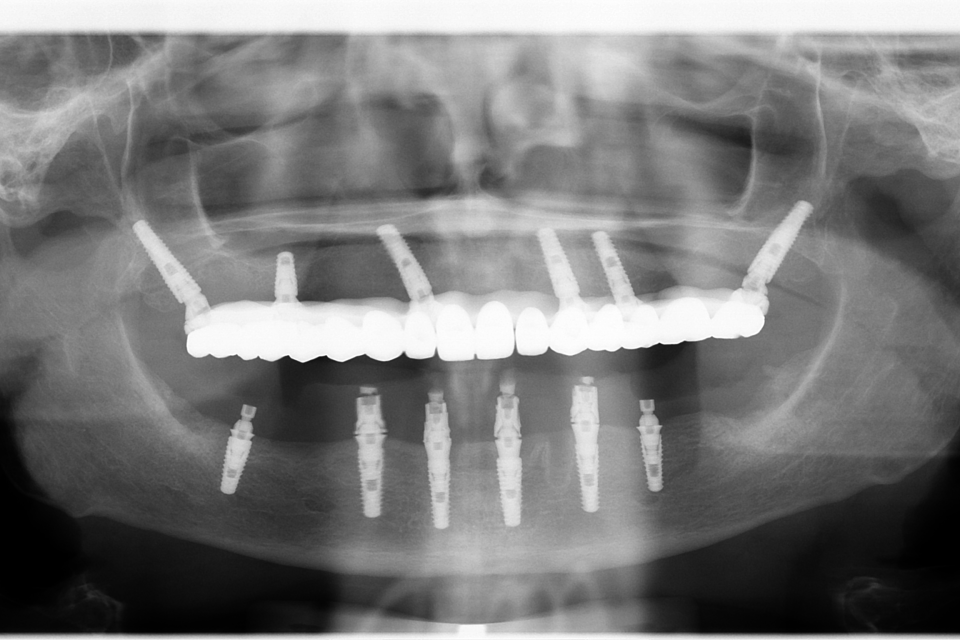

All on 6, implanturi orale speciale pterigoide

Imaginile sunt prezentate în ordinea evoluției tratamentului, de la situația inițială la rezultatul final.